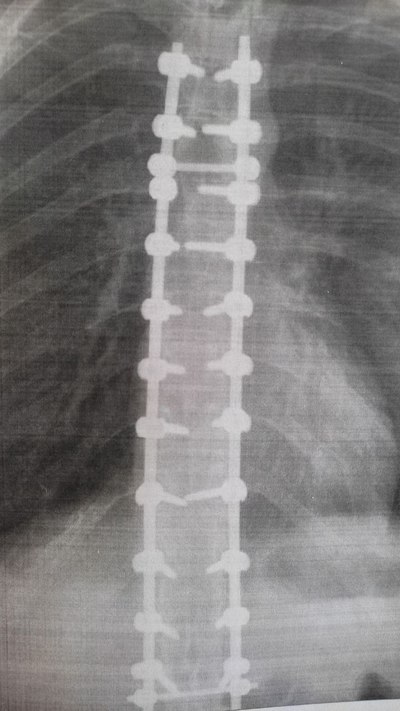

У меня был диагноз “правосторонний грудопоясничный S-образный сколиоз 4 степени”. В 2019 году (мне был 21 год) я сделала операцию по выравниванию позвоночника с помощью вживления титановой конструкции.

Чуть позднее меня отвезли на рентген послеоперационный и на КТ, чтобы проверить, все ли хорошо и не задевает ли конструкция что-то.

Прошло пару дней с операции. Лечащий врач посмотрел результаты КТ и снимки рентгена. И вынес мне вердикт, что мне нужна корректирующая операция. Сказал, что она быстрая, но мне снова нужно будет пройти через реанимацию. И мне стало страшно, страшнее, чем в первый раз, потому что я уже знала что мне придется повторить. Вторую операцию мне назначили на 27 июня. Всё пошло по кругу. Снова не есть с вечера, снова клизма. Утром увозят в операционную. Снова этот холод, дрожь. Операция длилась около 2х часов.

В больнице в общей сумме я провела 3 недели. Выписали меня 5 июля. Перед выпиской меня осмотрел лечащий врач, сделали снимки «после». Угол искривления с 50 градусов снизился до 13 градусов. Это очень хороший результат.